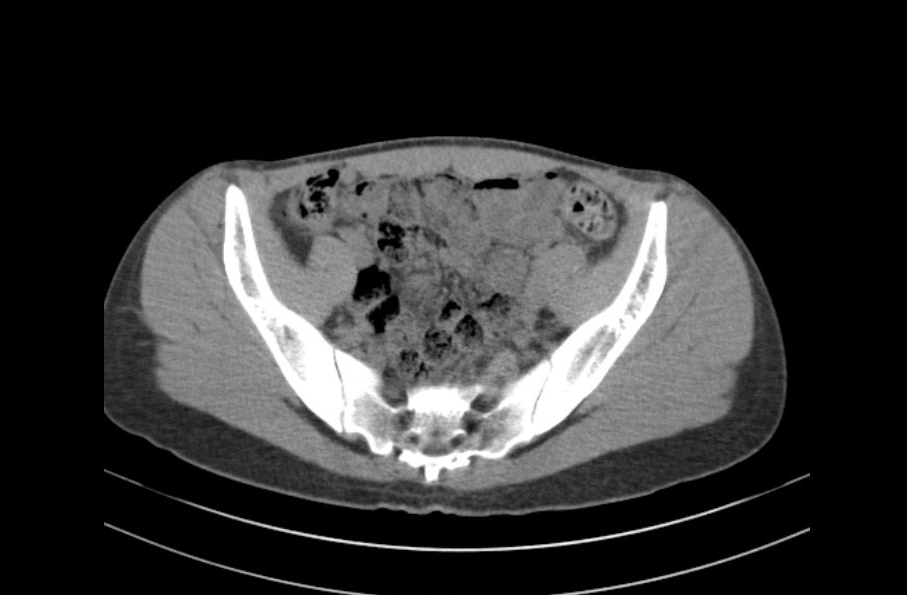

Since I got heart surgery a month ago, I can hear my heart beating all the time. Apparently it’s normal. I read online that they proved it wasn’t psychosomatic by performing open heart surgery on dogs and measuring the sound of their heartbeats afterwards. They found that dogs split open on the operating table -> dogs that hear their own heartbeat all the time. I also read that some dogs have a resting heart rate of over 200bpm. Woof woof woof. They’ve had me on gabapentin for a second now. It makes me feel so stupid like I got a lobotomy. I kept imagining a surgeon covered in dog guts. Woof… I wonder if my cardiologist knows about that study. I’m in the waiting room to see him now. I don’t think he would believe me about my symptoms unless I told him a dog experienced it too. Maybe that would be a more reliable source to him. It took so long to even get a referral to a cardiologist. I started noticing symptoms when I was 16, my mom noticed too in my behavior. She took me to the doctor. A lot of girls your age can misinterpret period cramps as chest pain, or it could be painful breast growth. Have you noticed your breasts getting larger? Actually, the new primary care I switched to said basically the same thing. It took 3 years of mentioning it at every appointment with multiple doctors for them to finally refer me to a cardiologist, who then told me the exact same thing again. At least he ordered some tests, surely with the intention to prove that I was making it up, give me a psych rec, etc, but they all came back abnormal. I thought that getting proof of my condition would stop my cardiologist from being so condescending, but being wrong wounded his ego or something. He treats me like I wanted this outcome just to rub his face in it. Yes, you technically do have a heart condition, that I found, that I diagnosed. Don’t forget who’s the doctor here. Just because you read Webmd doesn’t mean you know what you’re talking about. The thing that made me an even bigger nuisance in his eyes was when I wanted to actually go through with surgery, the standard treatment for my diagnosis. I’ve been worried to tell him that I don’t think I’m recovering properly.

The entire time during my meeting with my cardiologist I couldn’t stop squirming in my seat thinking about the fact that he saw me naked during my surgery. My boyfriend came over the other day and he wanted to see the big scar under my shirt, and then he started grabbing my chest. I was happy he didn’t think it was ugly. He said it was cute, a mark that showed I needed him to take care of me. My moms mostly been taking care of me though. I wish I could go back to helping her around the house, but she wont let me. After he started touching me I threw up all over my bed and he left. I didn’t want my mom to have to deal with the sheets so I cleaned them up myself. I squirmed in my seat. I wish my mom could have come with me to this appointment. I wonder how many people saw me naked in the operating room. I have another scar right above my crotch from the catheter they used… When they moved me to an examination room I realized I forgot to mention a few symptoms I had been having, probably because of the gabapentin making my memory so bad.

The appointment was stupid, like every other appointment. I don’t believe my cardiologist would notice or care if there were complications. If I died suddenly it must have been for something that couldn’t be helped. Even if I didn’t die from it, if my body feels like this for the rest of my life I’ll slit my throat. I would slit my throat in the middle of his office. Here’s something you can’t deny. The blood that I’m always aware of moving through my body, that I hear every drop of, all over your office. I want to turn myself inside out. You’re not allowed to look away! Look at me! Look at what I go through! This is the truth! My physical heart, ripped in half! Please, hold it in your hands, go ahead and crush it too, would you? Would you even believe me if I told you that you were making me sad? Or would you need to come up with that on your own too? Corroborated with a blood test, even. I guess all killing myself would prove in his eyes is that I’ve always been hysterical, maybe they would even let him use it to retract from my records that I ever had a heart condition or surgery in the first place. Poor doctor, some crazy girl insisted she had a heart condition, you wisely told her she was stupid and didn’t know what she was talking about and then she ruined your nice tie with her blood, I’ll throw her body in the psychosomatic mass grave for you. I wish I could have gone to college. I was going to go to college before my health got bad. I want to have a normal life. I want to be able to leave my house. I want to be able to live alone. My heart is so loud. I want my mom to get here soon, I want to go home and listen to music.